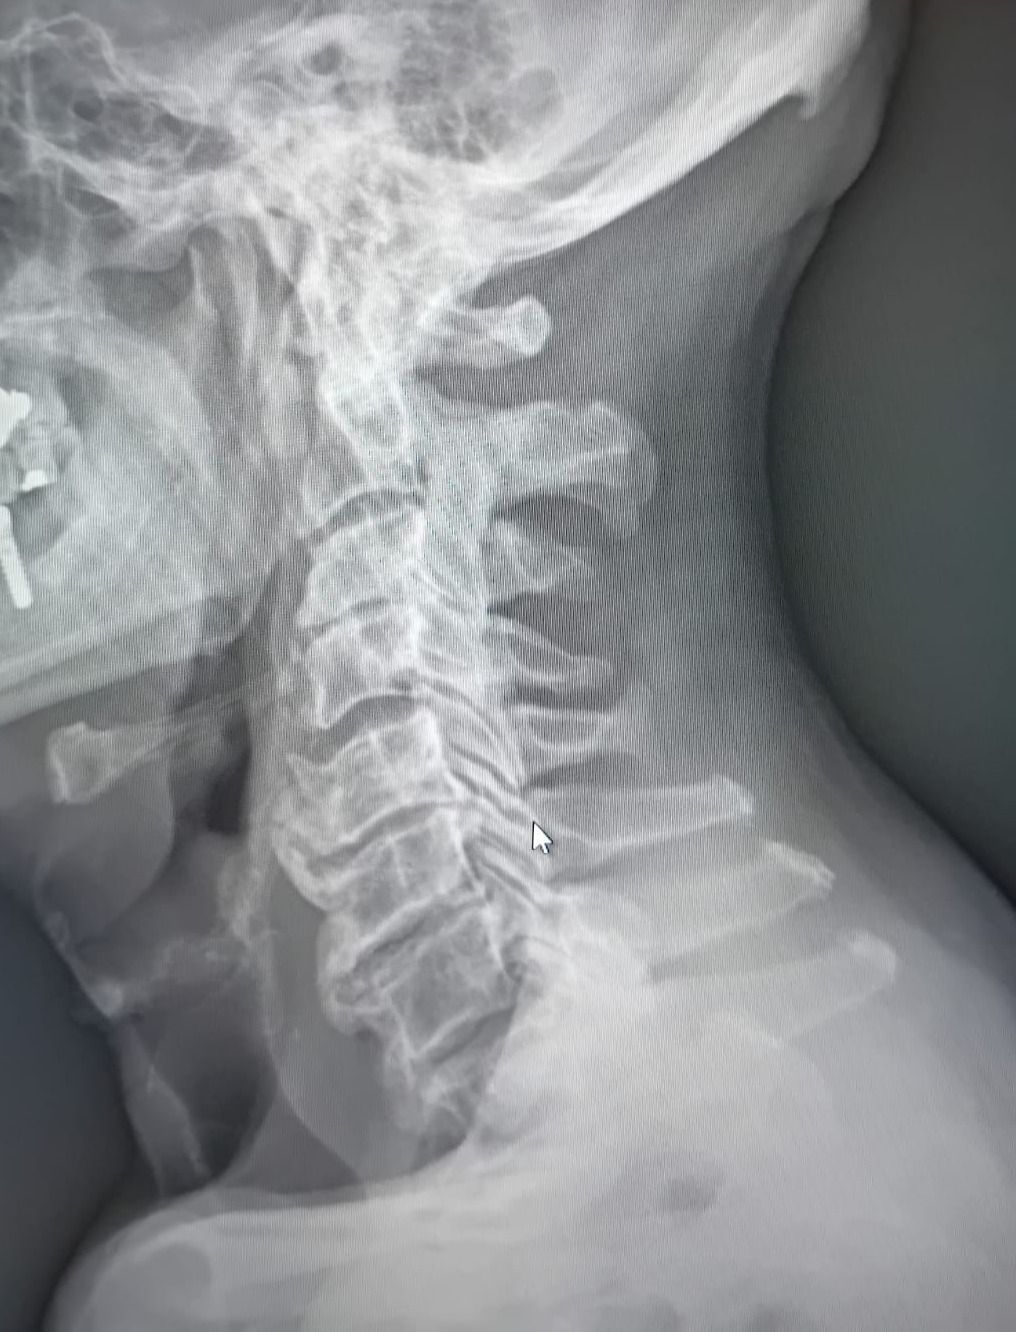

Foto e video